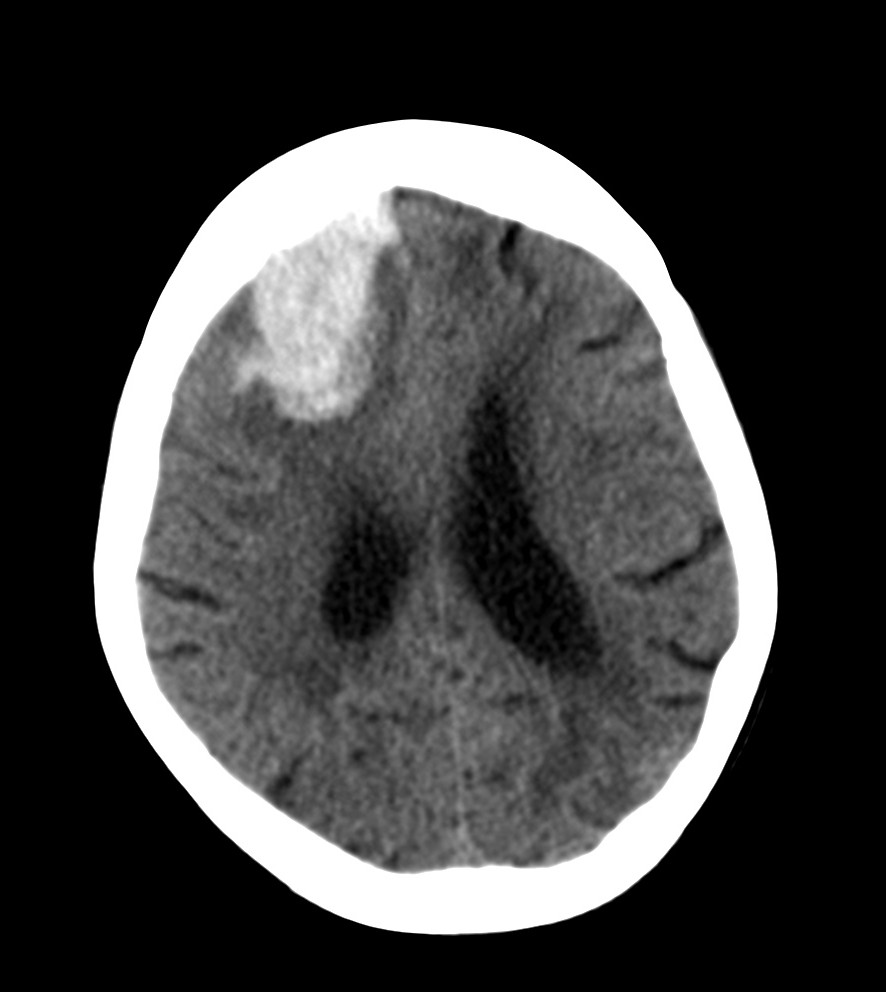

CASO 1.

Paciente mujer de 51 años, hipertensa y con antecedentes personales de dislipemia, que acude a urgencias por por cefalea, vómitos y hemiparesia contralateral.

TA 200/130 ; FC 98 lat/min ; Sat o2 96%.

Hemorragia cerebral hipertensiva:

La hipertensión arterial constituye el principal factor de riesgo de las hemorragias intracerebrales no traumáticas en el 70 – 90% de los casos. Afecta en el 75% de las veces a los ganglios de la base y el tálamo (80% afecta al núcleo lenticular, principalmente el putamen). Entre el 10 – 50% pueden ser lobares, 10-15% protuberancia, 10 – 30% cerebelo (éstas dos últimas localizaciones son las de mayor mortalidad). Los pacientes que sobreviven presentan mejor recuperación funcional que en la isquemia, aunque un porcentaje significativo padecer secuelas y dependencia para las actividades diarias.

En caso de afectación del Putamen (lo más frecuente), puede existir hemiparesia e hemihipostesia contralaterales, deterioro de nivel de consciencia y desviación oculocefálica hacia el lado de la hemorrágica con preservación de reflejos del tronco. (ver tabla)

TAC es la prueba de elección. El extravasado de sangre se observa como un aumento de la atenuación. Existe una correlación lineal entre el hematocrito y el aumento de atenuación por sangrado (56 unidades Hounsfield aprox.)